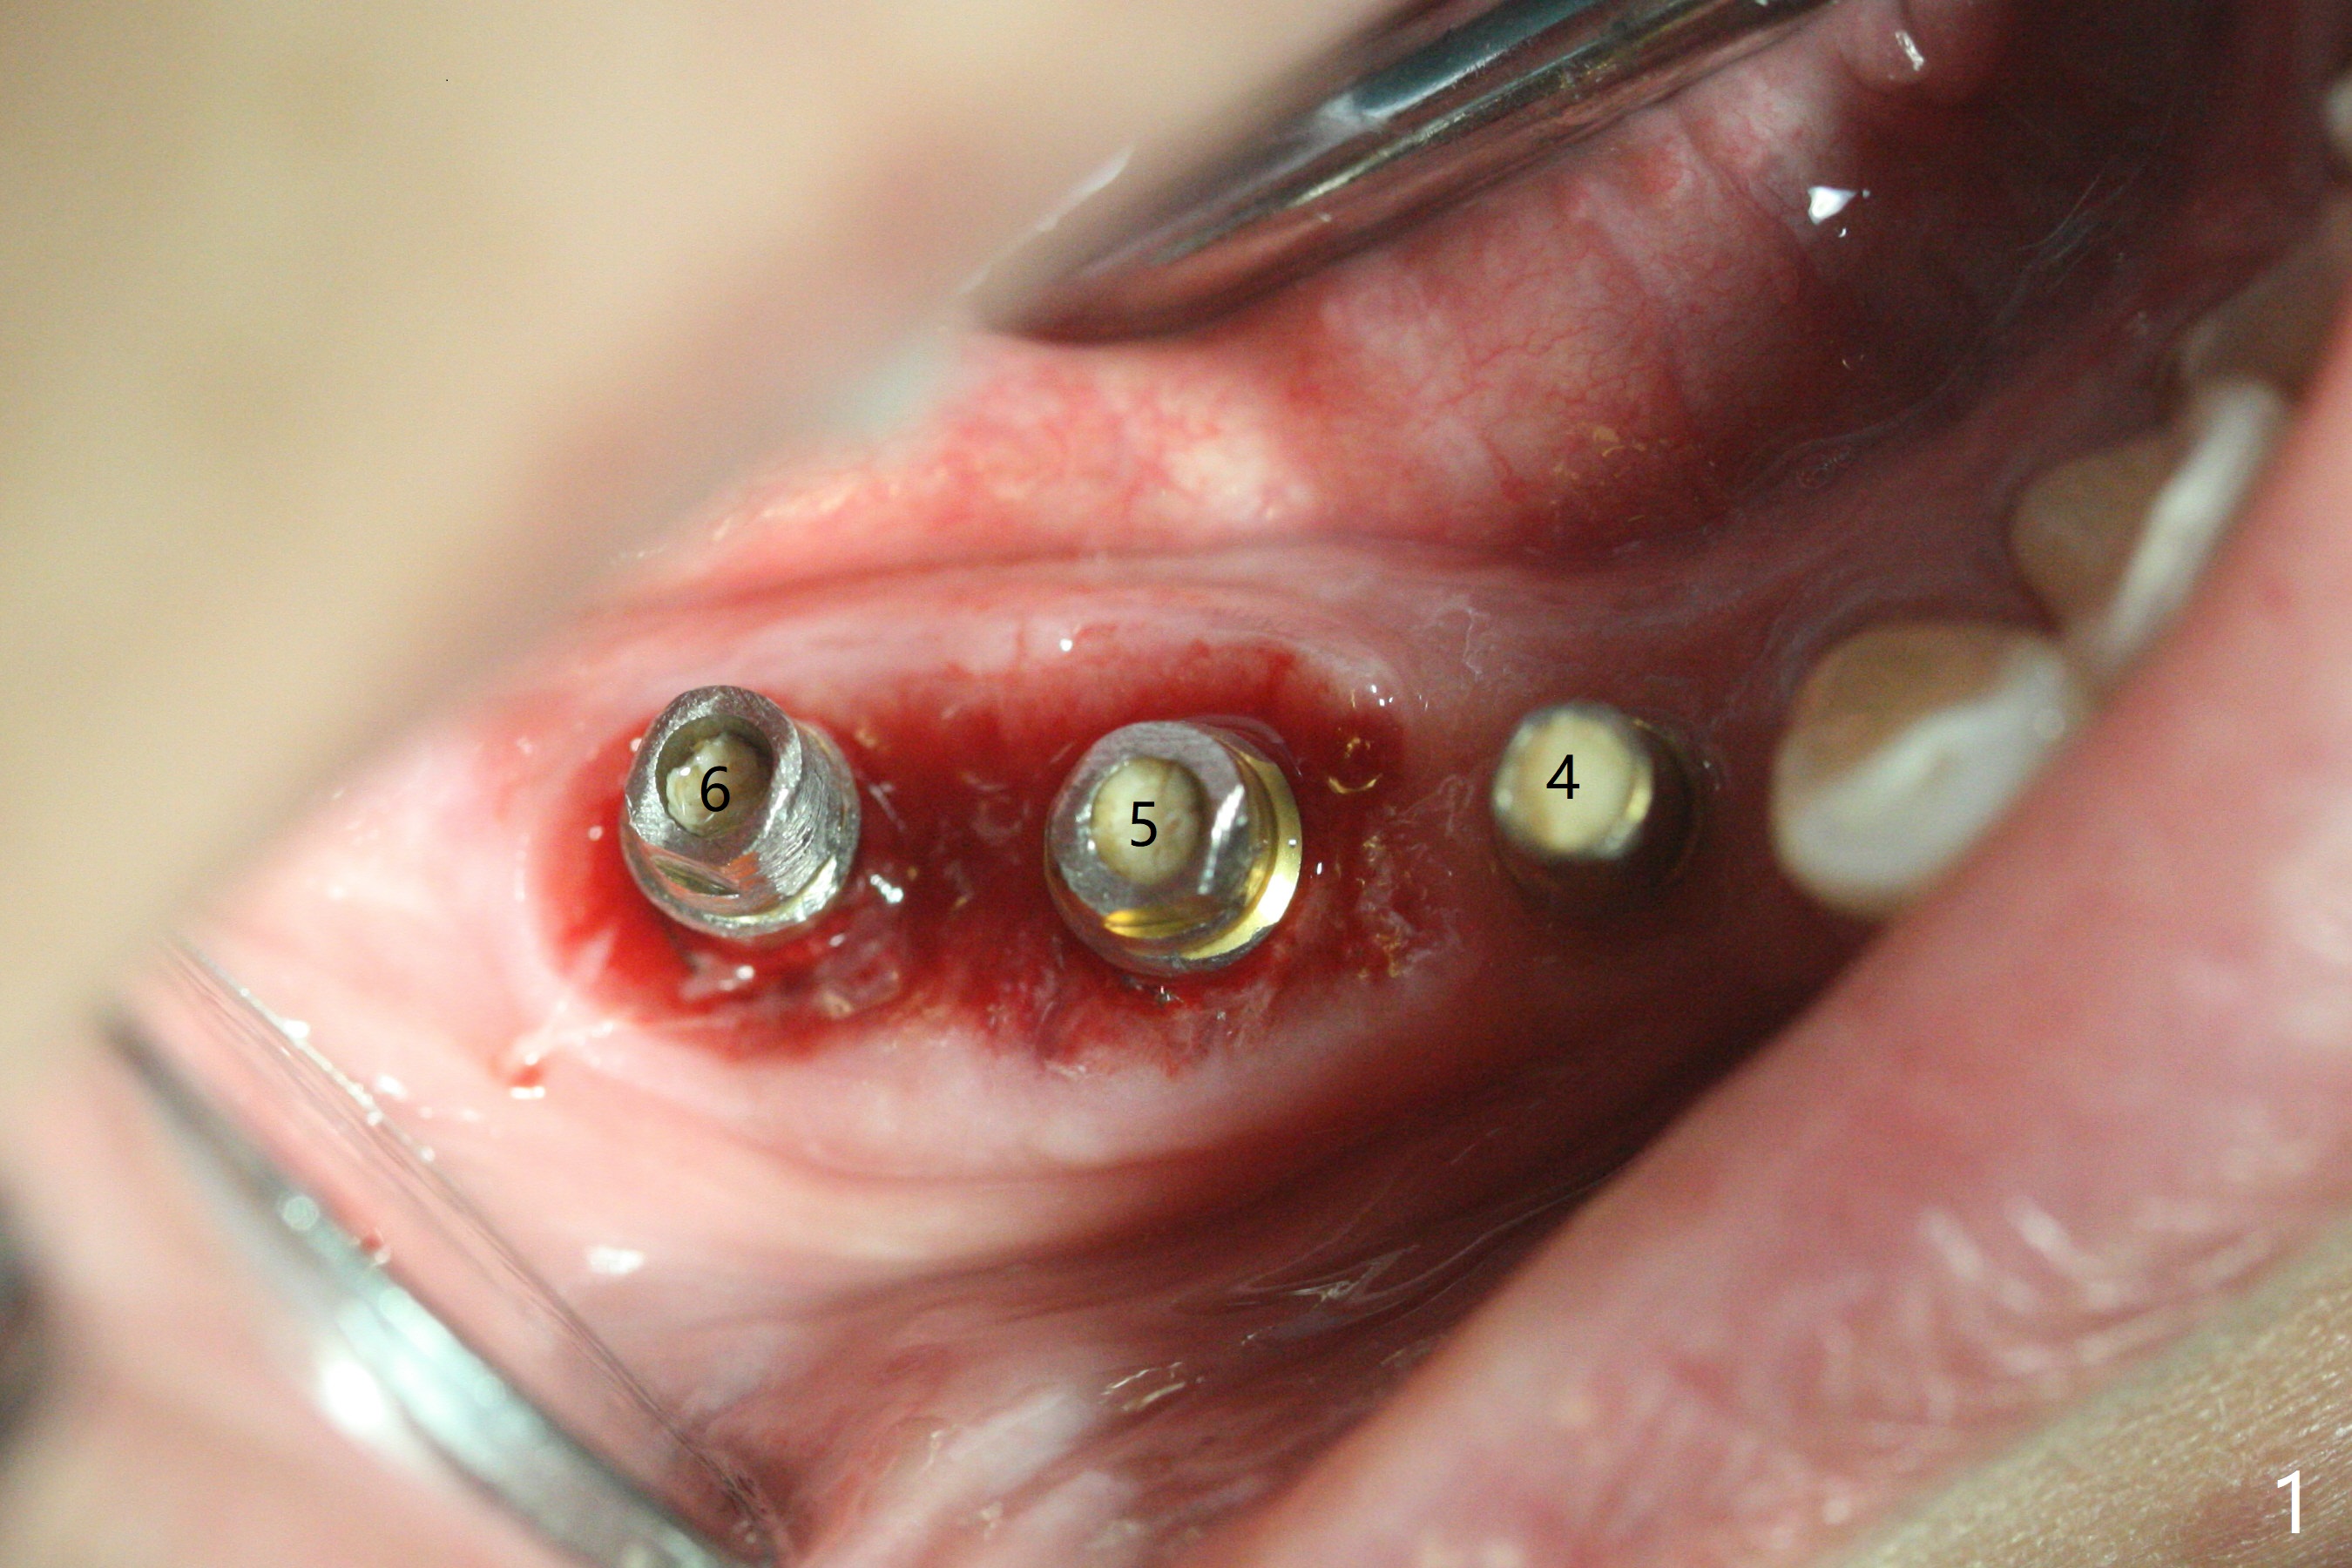

右下4-6种植后3.5月制作临时牙桥(保险的钱用完了),虽然不舒服,病人也没有及时复诊。新年过后(术后11月),她回来修复,但是临时牙桥下沉,造成牙龈退缩(图一),6螺纹暴露(图二:>),粘性骨粉中间形成一个洞眼(图三),插入6基台固定(图四),同样PRF膜也形成两三个洞眼固定在基台上(图五)。当粘性骨粉放置时,暴露螺纹已经被血凝块覆盖,舍不得去除,所以骨粉就不能接触螺纹(图六),最后用牙周敷料固定(图七),想象比树脂敷料服帖。不过2天后,牙周敷料脱落,骨粉丧失,伤口好像已经愈合(图八),没有做任何处理。今后类似病例应该在基台上涂抗病毒凡士林(以后好撤除),使用树脂敷料。Return to No Deviation Xin Wei, DDS, PhD, MS 1st edition 01/05/2021, last revision 01/08/2021